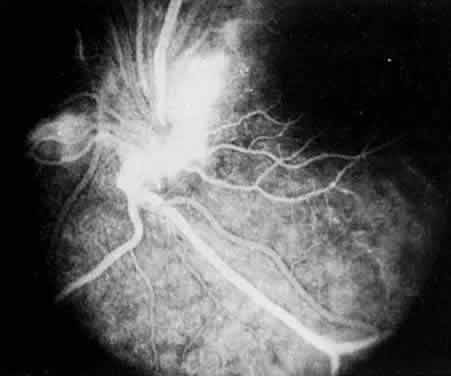

In pars planitis, fluorescein angiography shows diffuse leakage from the retinal venules and capillaries, without any predilection for the inferior retinal vasculature (Figs. 5 and 6).28 Similarly, vitreous fluorophotometry in patients with pars planitis also shows no predilection for vascular leakage in the inferior peripheral retina.29 These findings suggest that snowbank is most likely a sequela from ocular inflammation, that inferior peripheral retina periphery is not the source of inflammation in pars planitis, and that pars planitis is not a localized inflammatory response of the inferior retina.

Fig. 5. Pars planitis. Fluorescein angiogram showing diffuse venous and capillary leakage.

Fig. 6. Pars planitis. Fluorescein angiogram of pars plana membrane showing diffuse leakage indicating neovascularization.